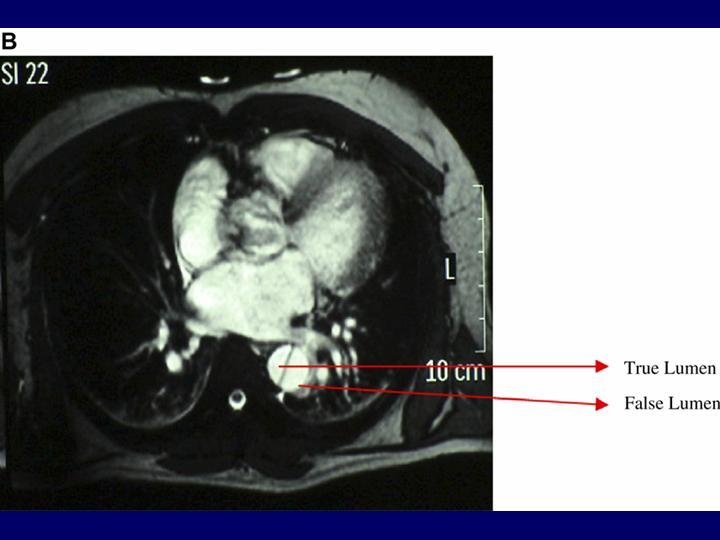

Disección Aórtica

Vascular

| Autor: Dr. Leandro Revello